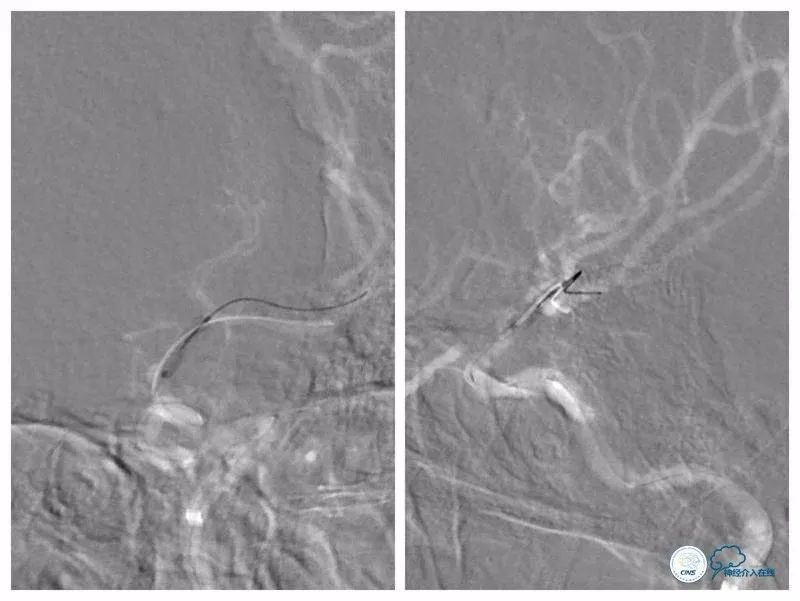

路径图下沿Navien导管送入Echelon 10微导管携Synchro微导丝(0.014″,200cm)尝试过狭窄段未成功(图8)。

图8

更换为Pilot-50微导丝(0.014″,200cm),越过狭窄起始段,再次更换为Synchro微导丝,送至左大脑中动脉M2段(图9)。

图9

跟进Echelon 10微导管以期通过病变未获成功,遂逐节剪断微导管撤出微导管,保留微导丝。送入Ultra-soft球囊(2.0mm×20mm)至狭窄段近端及远端行球扩后造影显示狭窄程度和前向血流均有所改善(图10)。

图10